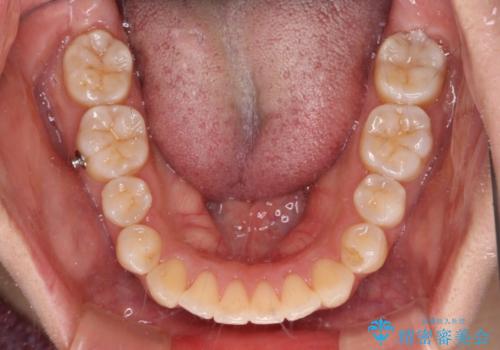

また、舌の突出癖の影響で上下前歯が接触していないオープンバイトとなっており、奥歯に負担のかかる咬み合わせとなっていました。

乳歯を抜歯し、舌側の永久歯を引っ張り出すこととしましたが、希望のインビザラインでは移動量が大きすぎて対応できない可能性があったため、ワイヤー装置にて改善することとしました。

ワイヤー装置にてある程度歯列が改善されたところで、上下をインビザラインにて矯正治療を行うこととしました。